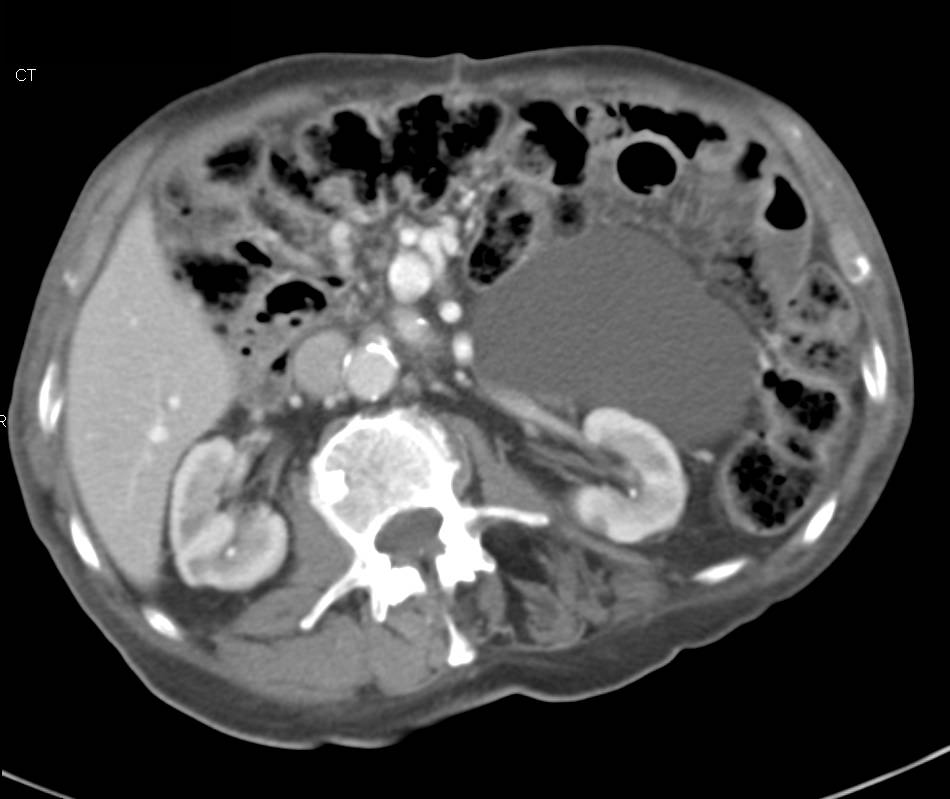

Carcinoid Tumor with encased Superior Mesenteric Artery (SMA)/Superior Mesenteric Vein (SMV)